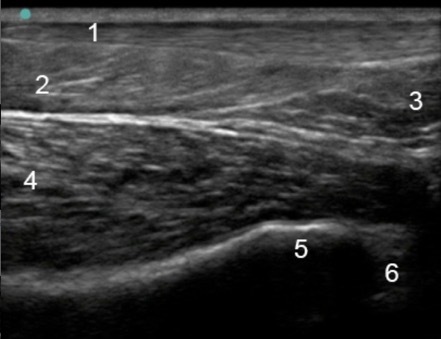

Foot & Ankle Posterior Ankle Longitudinal 3 Image

1. Achilles

2. Soleus

3. Kager’s Fat Pad

4. Flexor Hallucis Longus

5. Tibia

6. Talus